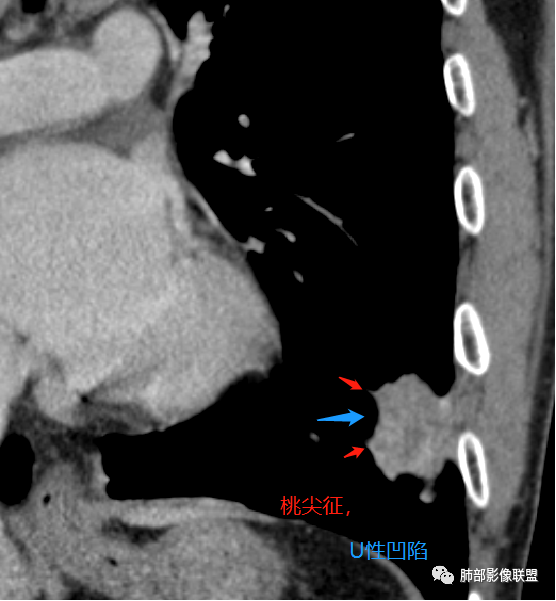

左下叶不规则实变,有平直及u型凹陷,胸膜糊墙,不均匀强化,其内可坏死灶,肿块内缘起始部可见钙化灶,病史较长,虽有胃肾肿瘤史,但影像表现及病灶走行(爬行征)均不支持转移,综合分析考虑炎性肉芽肿,OP并脓肿,其次考虑TB,留个尾巴鉴别腺癌

既往胃肾肿瘤。左下肺病灶直边,凹陷,支气管进入并有截断,宽基底与胸膜相连,内部有囊圆形坏死,旁边有卫星灶,考虑良性,肉芽肿,恶性,腺癌转移待除

平直收缩、尖桃都有 病灶变化快 炎性

良性的依据有五点::第一,周围收缩,凹陷,桃尖,边缘大部分平直,周围卫星灶。第二,栽脏不明确,第三,强化有环形强化的感觉。第四,有支气管爬行的味道。第五,专门提出三个月前胸片多发小结节,三个月后变大成肿块。

第一,周围收缩,凹陷,桃尖,边缘大部分平直,周围卫星灶。